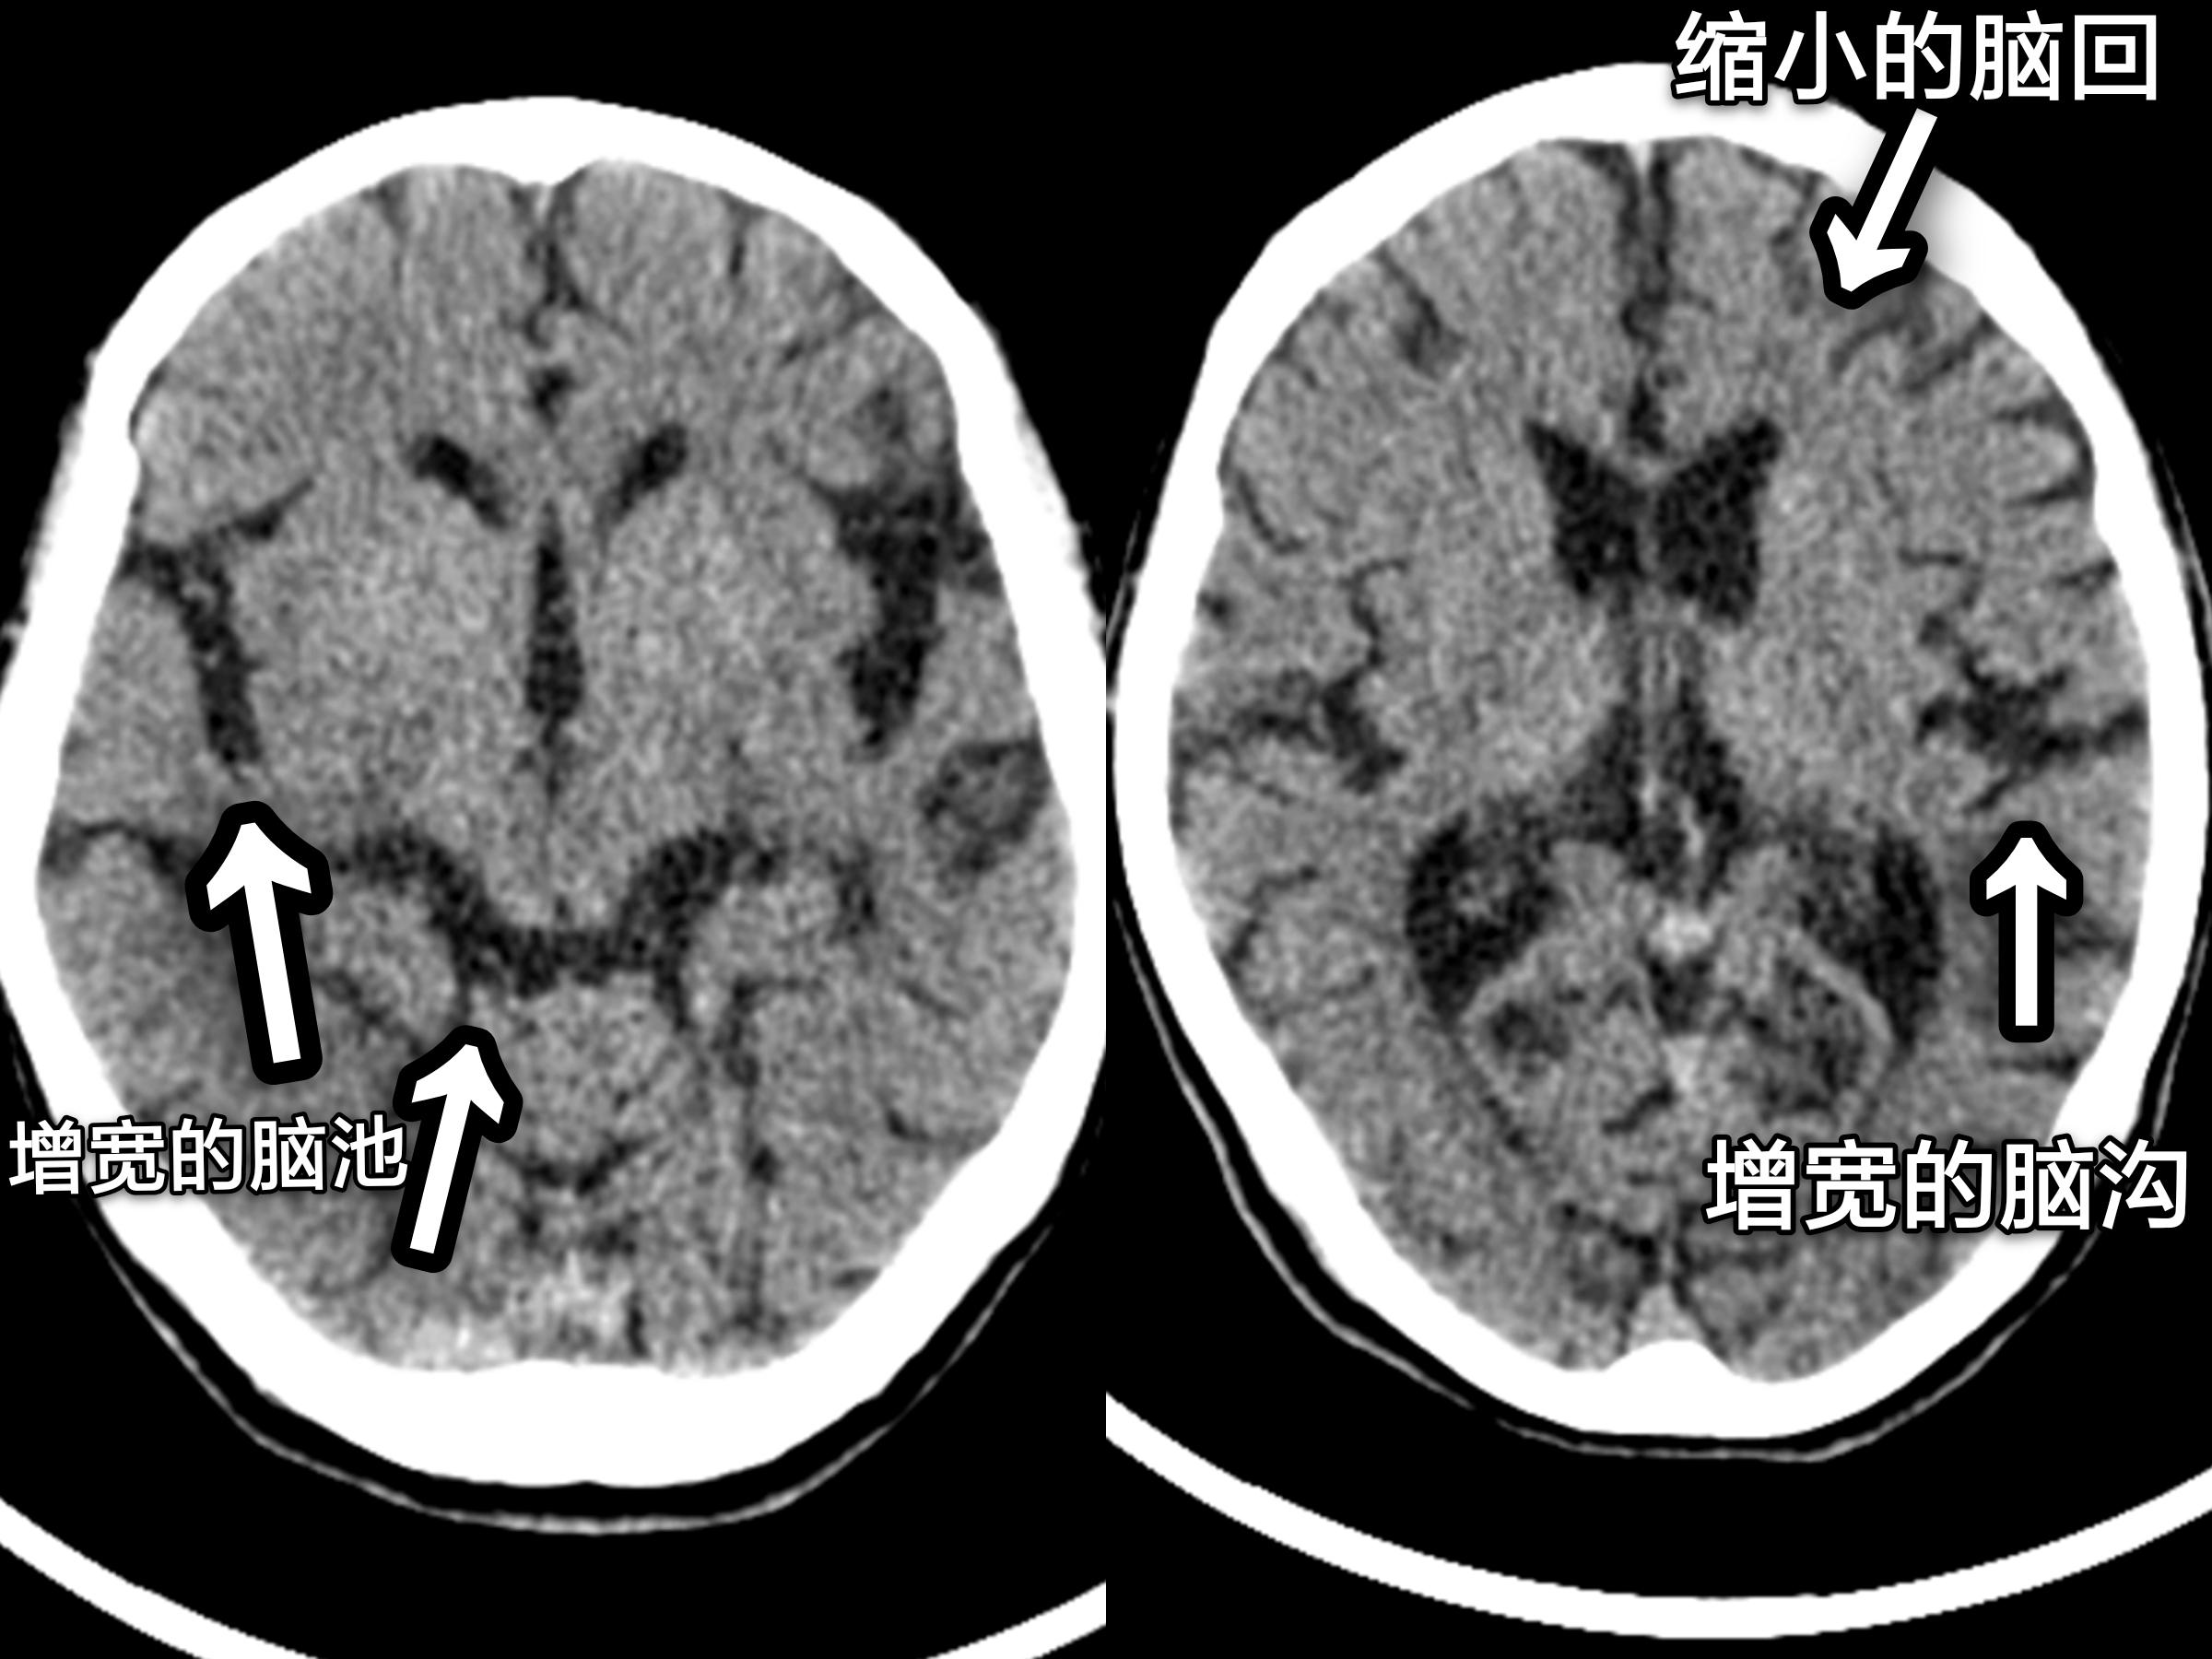

再来看看脑萎缩的图像(箭头所标处):

CT检查萎缩的大脑

从上面的这几幅图中,大家可以明显看出脑室、脑池的扩大和脑沟增宽增深,脑回变窄。